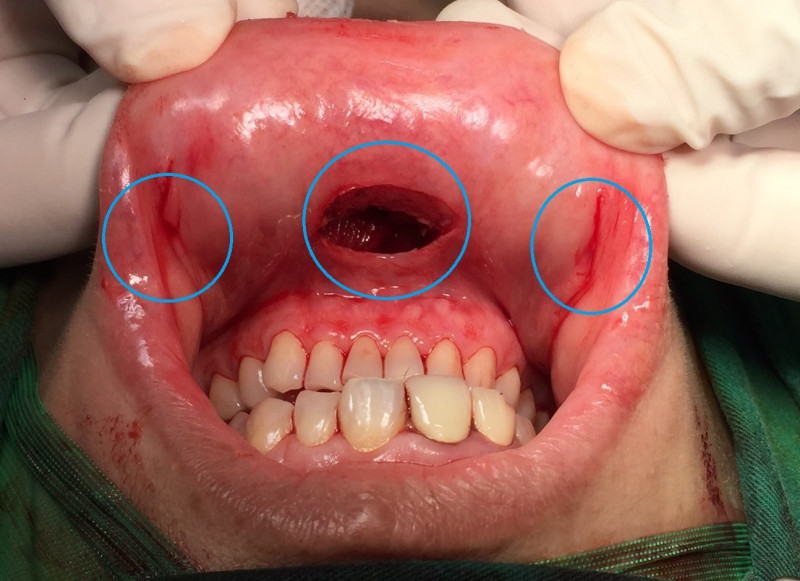

巫奕儒指出,甲狀腺結節分為良性和惡性,且無痕微創手術也不同。良性結節可用第4代達文西機械手臂進行「自然孔洞達文西甲狀腺手術」,結合ICG螢光即時定位副甲狀腺,幫助保留副甲狀腺及返喉神經,將甲狀腺結節病灶半側切除。惡性結節則須另外考慮腫瘤大小、侵犯程度與淋巴轉移範圍。

巫奕儒表示,國際普遍認為若腫瘤小於2公分,無甲狀腺外侵犯且有局部中央淋巴結轉移,可採用「自然孔洞達文西甲狀腺手術」;若大於2公分或有外側淋巴結轉移,採用「雙側經乳暈和腋下達文西甲狀腺手術」,避免頸部傷口疤痕,可由腳位至頭位的外側淋巴結清除,配合神經導引與ICG螢光保留副甲狀腺。若已侵犯鄰近器官,就不要勉強用無痕手術,應以根除性切除為主要考量。